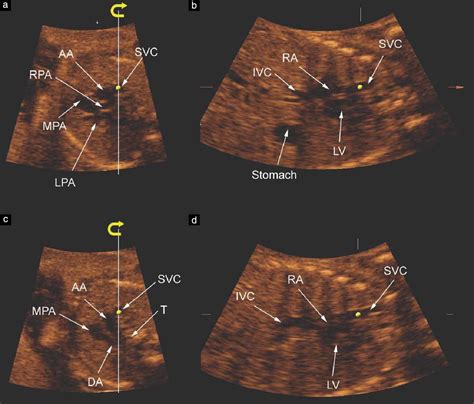

Several standard views are used to visualize the outflow tracts on ultrasound. These views provide different perspectives of the heart's structures and help in comprehensive assessment. The most common views include:

• Parasternal Long-Axis View: This view provides a longitudinal section of the heart, showing the LVOT, aortic valve, and ascending aorta.

• Parasternal Short-Axis View: This view offers a cross-sectional image of the heart at the level of the aortic valve, allowing for detailed assessment of the valve leaflets and outflow tract.

• Apical Five-Chamber View: This view includes the LVOT, aortic valve, and the right ventricular outflow tract (RVOT).

• Subcostal View: This view is useful for assessing the RVOT and pulmonary valve, especially in patients with limited acoustic windows.

In congenital heart disease, ultrasound plays a pivotal role in diagnosing and monitoring structural abnormalities of the outflow tracts. Conditions such as tetralogy of Fallot, pulmonary atresia, and coarctation of the aorta can be accurately assessed using ultrasound.

• ductal arch vs aortic ultrasound